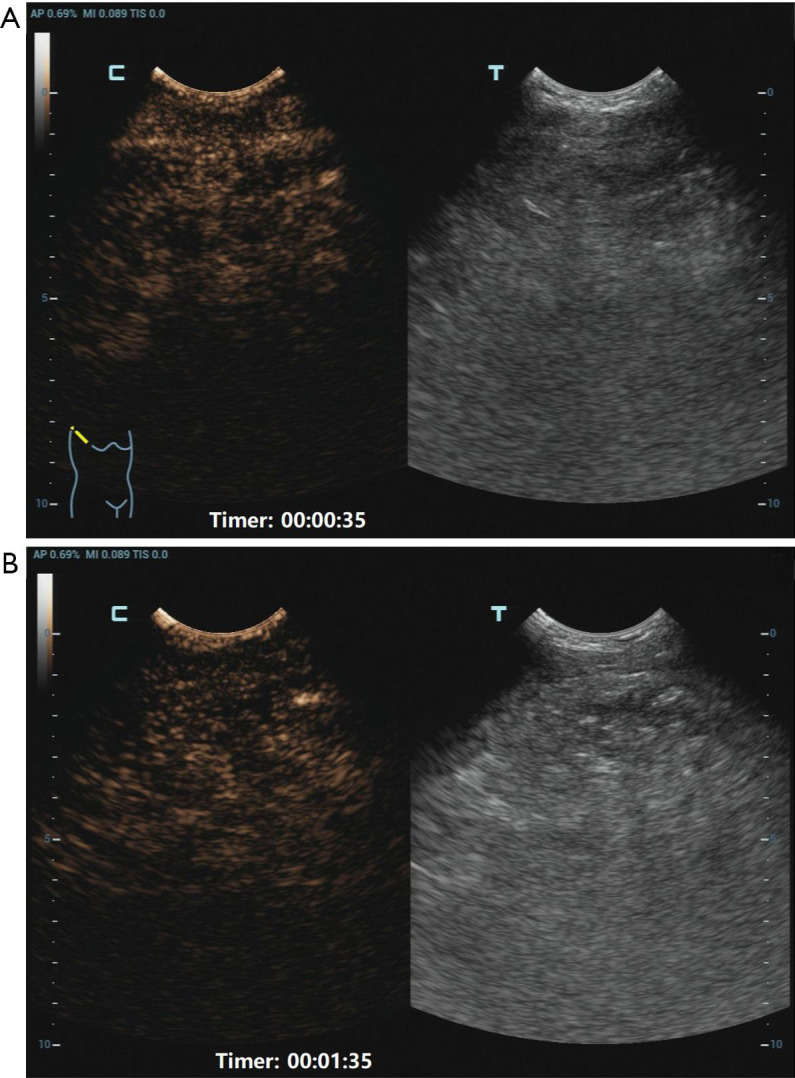

Case description: A teenage girl was diagnosed with a giant thymolipoma, which was discovered incidentally during a routine chest radiograph. Notably, the patient remained asymptomatic despite the tumor's considerable size and its apparent impact on surrounding thoracic structures. To facilitate a thorough preoperative assessment, a multimodal imaging approach was employed, including contrast-enhanced ultrasound (CEUS), computed tomography (CT), and magnetic resonance imaging (MRI). These advanced imaging techniques played a crucial role in delineating the tumor's extent, characteristics, and relationship to adjacent anatomical structures, thereby informing surgical planning. Ultimately, the tumor was successfully excised through a median sternotomy. Postoperative pathological examination confirmed the diagnosis of thymolipoma. Remarkably, after a follow-up period of five years, the patient showed no signs of recurrence and maintained a healthy status.